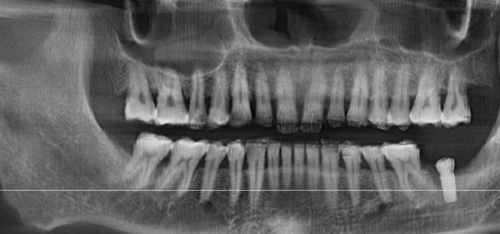

种牙是特别多缺牙患者的理想选择,但种牙收费明细一直是大家关注的焦点。在2026年,种牙的费用受到多种因素影响,具体收费情况究竟如何呢?本文将为你详细揭秘种牙收费明细,让你在种牙前做好充分的准备,心中有数。

在2026年,种牙一般需要5000 - 30000元。不过,这只是一个大致的范围,具体费用会与当地经济水平、种植体品牌、手术难度、修复材料等因素密切相关。比如在经济发达的地区,种牙费用可能会相对高一些;而使用高端品牌的种植体,费用也会比普通品牌贵。所以,种牙收费明细并不是固定不变的,要根据实际情况来确定。